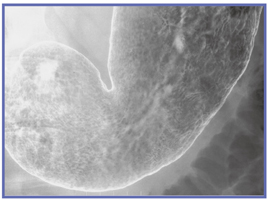

きれいに写るものも,きれいに写そうとしなければ写らないのであり,技師は良い画像を撮ることを意識しなければならない。バリウムをきれいに付着させる(図4),Cアームを活用して病変を正面からとらえる(図5)といったことにきちんと取り組むことが重要である。

![]() 図4 バリウムの付着が良好な画像 |